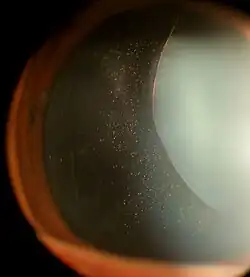

| Ectopia lentis in Marfan syndrome: Zonular fibers are seen. | |

In Marfan syndrome, the health of the eye can be affected in many ways, but the principal change is partial lens dislocation, where the lens is shifted out of its normal position.[17] This occurs because of weakness in the ciliary zonules, the connective tissue strands which suspend the lens within the eye. The mutations responsible for Marfan syndrome weaken the zonules and cause them to stretch. The inferior zonules are most frequently stretched resulting in the lens shifting upwards and outwards, but it can shift in other directions as well. Nearsightedness (myopia), and blurred vision are common due to connective tissue defects in the eye.[18] Farsightedness can also result particularly if the lens is highly subluxated. Subluxation (partial dislocation) of the lens can be detected clinically in about 60% of people with Marfan syndrome by the use of a slit-lamp biomicroscope.[18] If the lens subluxation is subtle, then imaging with high-resolution ultrasound biomicroscopy might be used.[19]

Other signs and symptoms affecting the eye include increased length along an axis of the globe, myopia, corneal flatness, strabismus, exotropia, and esotropia.[17] Those with MFS are also at a high risk for early glaucoma and early cataracts.[18]